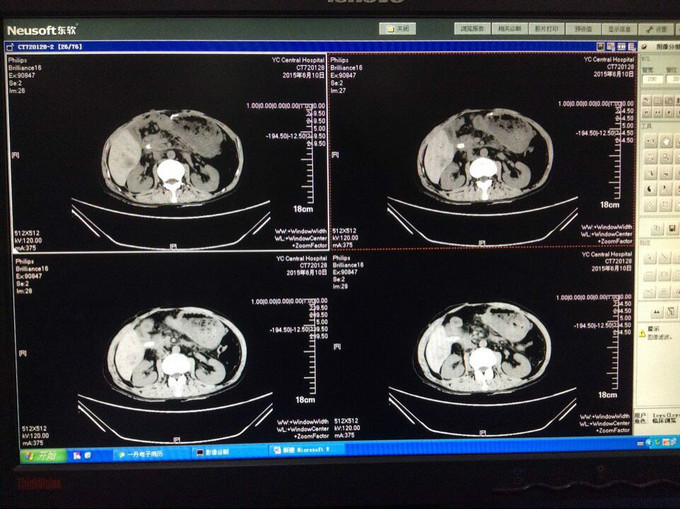

入院查血: Blood-Rt(五分类): 白细胞 6.97*10^9/L,红细胞 3.84*10^12/L,血红蛋白 122 g/L,红细胞压积 37.3 %,血沉 42 mm/h 查体:无特殊异常,腹腔引流管偶有黄褐色浑浊液体流出,量约50-80ml,腹软,无压痛、反跳痛,二便正常。 辅检:上腹部CT提示:胆肠吻合口一直径约2cm结石 辅助检查见上图

漏口位置,依据上消化道钡餐造影未见消化道穿孔,而从腹腔引流管处注入碘水造影可见肠管及隐约胃形显示,估计漏口位置为胰腺空肠及胆管吻合处肠管漏口, CT提示:胆道结石,尝试拔管后漏口无法愈合,再次予以腹腔引流置管。 我们分析漏口无法愈合的原因为胰液及胆汁对自身组织的消化,术中胆肠吻合口处放置T管,及胰腺空肠段放置引流管,引流肠液,目的为减轻消化液对漏口的影响,术后原漏口愈合,但出现新唇状漏,采用T管经皮下隧道引流 ,原皮肤漏口缝闭,同时加用负压吸引。 讨论2点: 1.该病人初次少量胆漏合并胆道结石时是否需要手术治疗? 2.再次出现唇状漏时,患者消化液外漏引起局部皮炎,皮肤伤口周围组织腐蚀严重,采用T管经皮下隧道引流,能否起到良好的治疗效果?